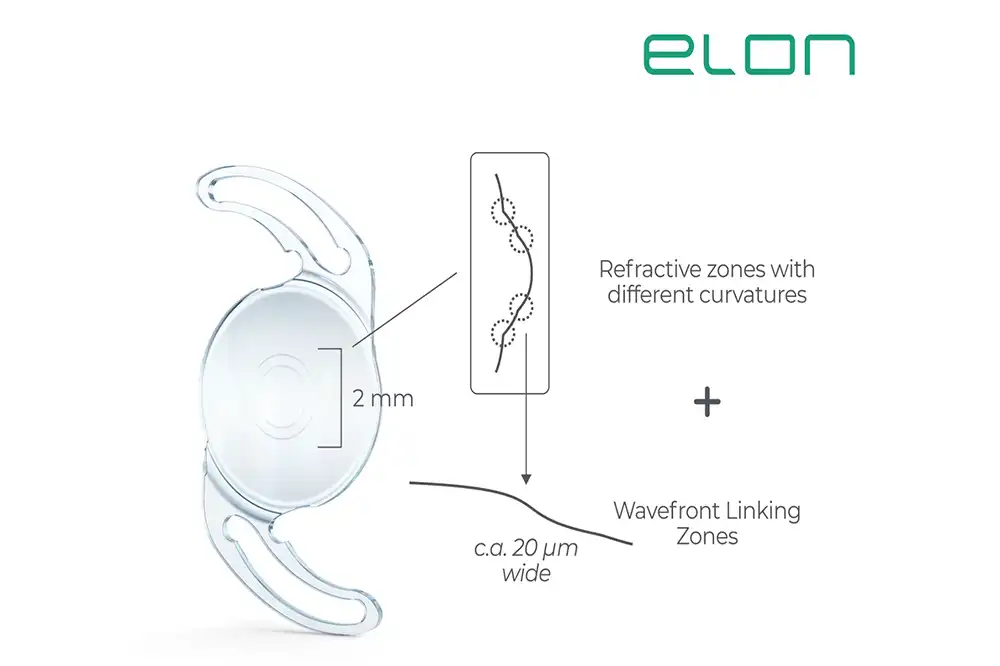

Om het doel te bereiken van een echte Extended Depth of Focus (EDoF) intraoculaire lens met 𝐦𝐢𝐧𝐢𝐦𝐚𝐥𝐞 𝐨𝐩𝐭𝐢𝐬𝐜𝐡𝐞 𝐯𝐞𝐫𝐬𝐭𝐨𝐫𝐢𝐧𝐠𝐞𝐧, ontwikkelde Medicontur de innovatieve Wavefront Linking-technologie.

Linking zones

Het principe achter deze technologie is eenvoudig maar ingenieus: door licht te beschouwen als een golf in plaats van als deeltjes, creëert ELON 2 centrale gebogen zones die naadloos verbonden zijn door uiterst gladde linking-zones.

De EDoF-zone bevindt zich fysiek vóór de basiskromming van de lens. Wanneer het licht de lensoppervlakte bereikt, verschuift de fase van de lichtgolf subtiel, wat leidt tot constructieve interferentie langsheen de optische as.

Uitstekend intermediair

Op deze manier wordt een deel van de lichtenergie gebruikt om het intermediaire brandpunt te versterken. De technologie is bovendien pupilafhankelijk: bij kleine pupillen (≤3 mm) wordt een uitstekende intermediaire en zelfs nabije gezichtsscherpte bereikt.